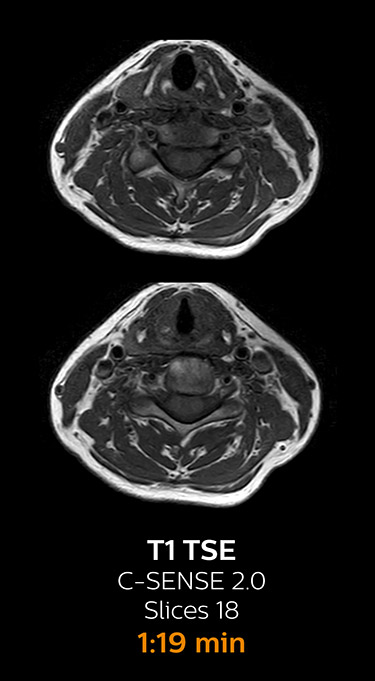

Fast MRI of cervical spine

With Compressed SENSE, the scan time for the routine cervical spine examination at KNC was reduced from 13:11 to 9:52 minutes, which corresponds to 25% reduction.

MRI examination of the cervical spine with Compressed SENSE

Ingenia 3.0T CX

Scan time 9:52 min. (was 13:11 min. without Compressed SENSE)